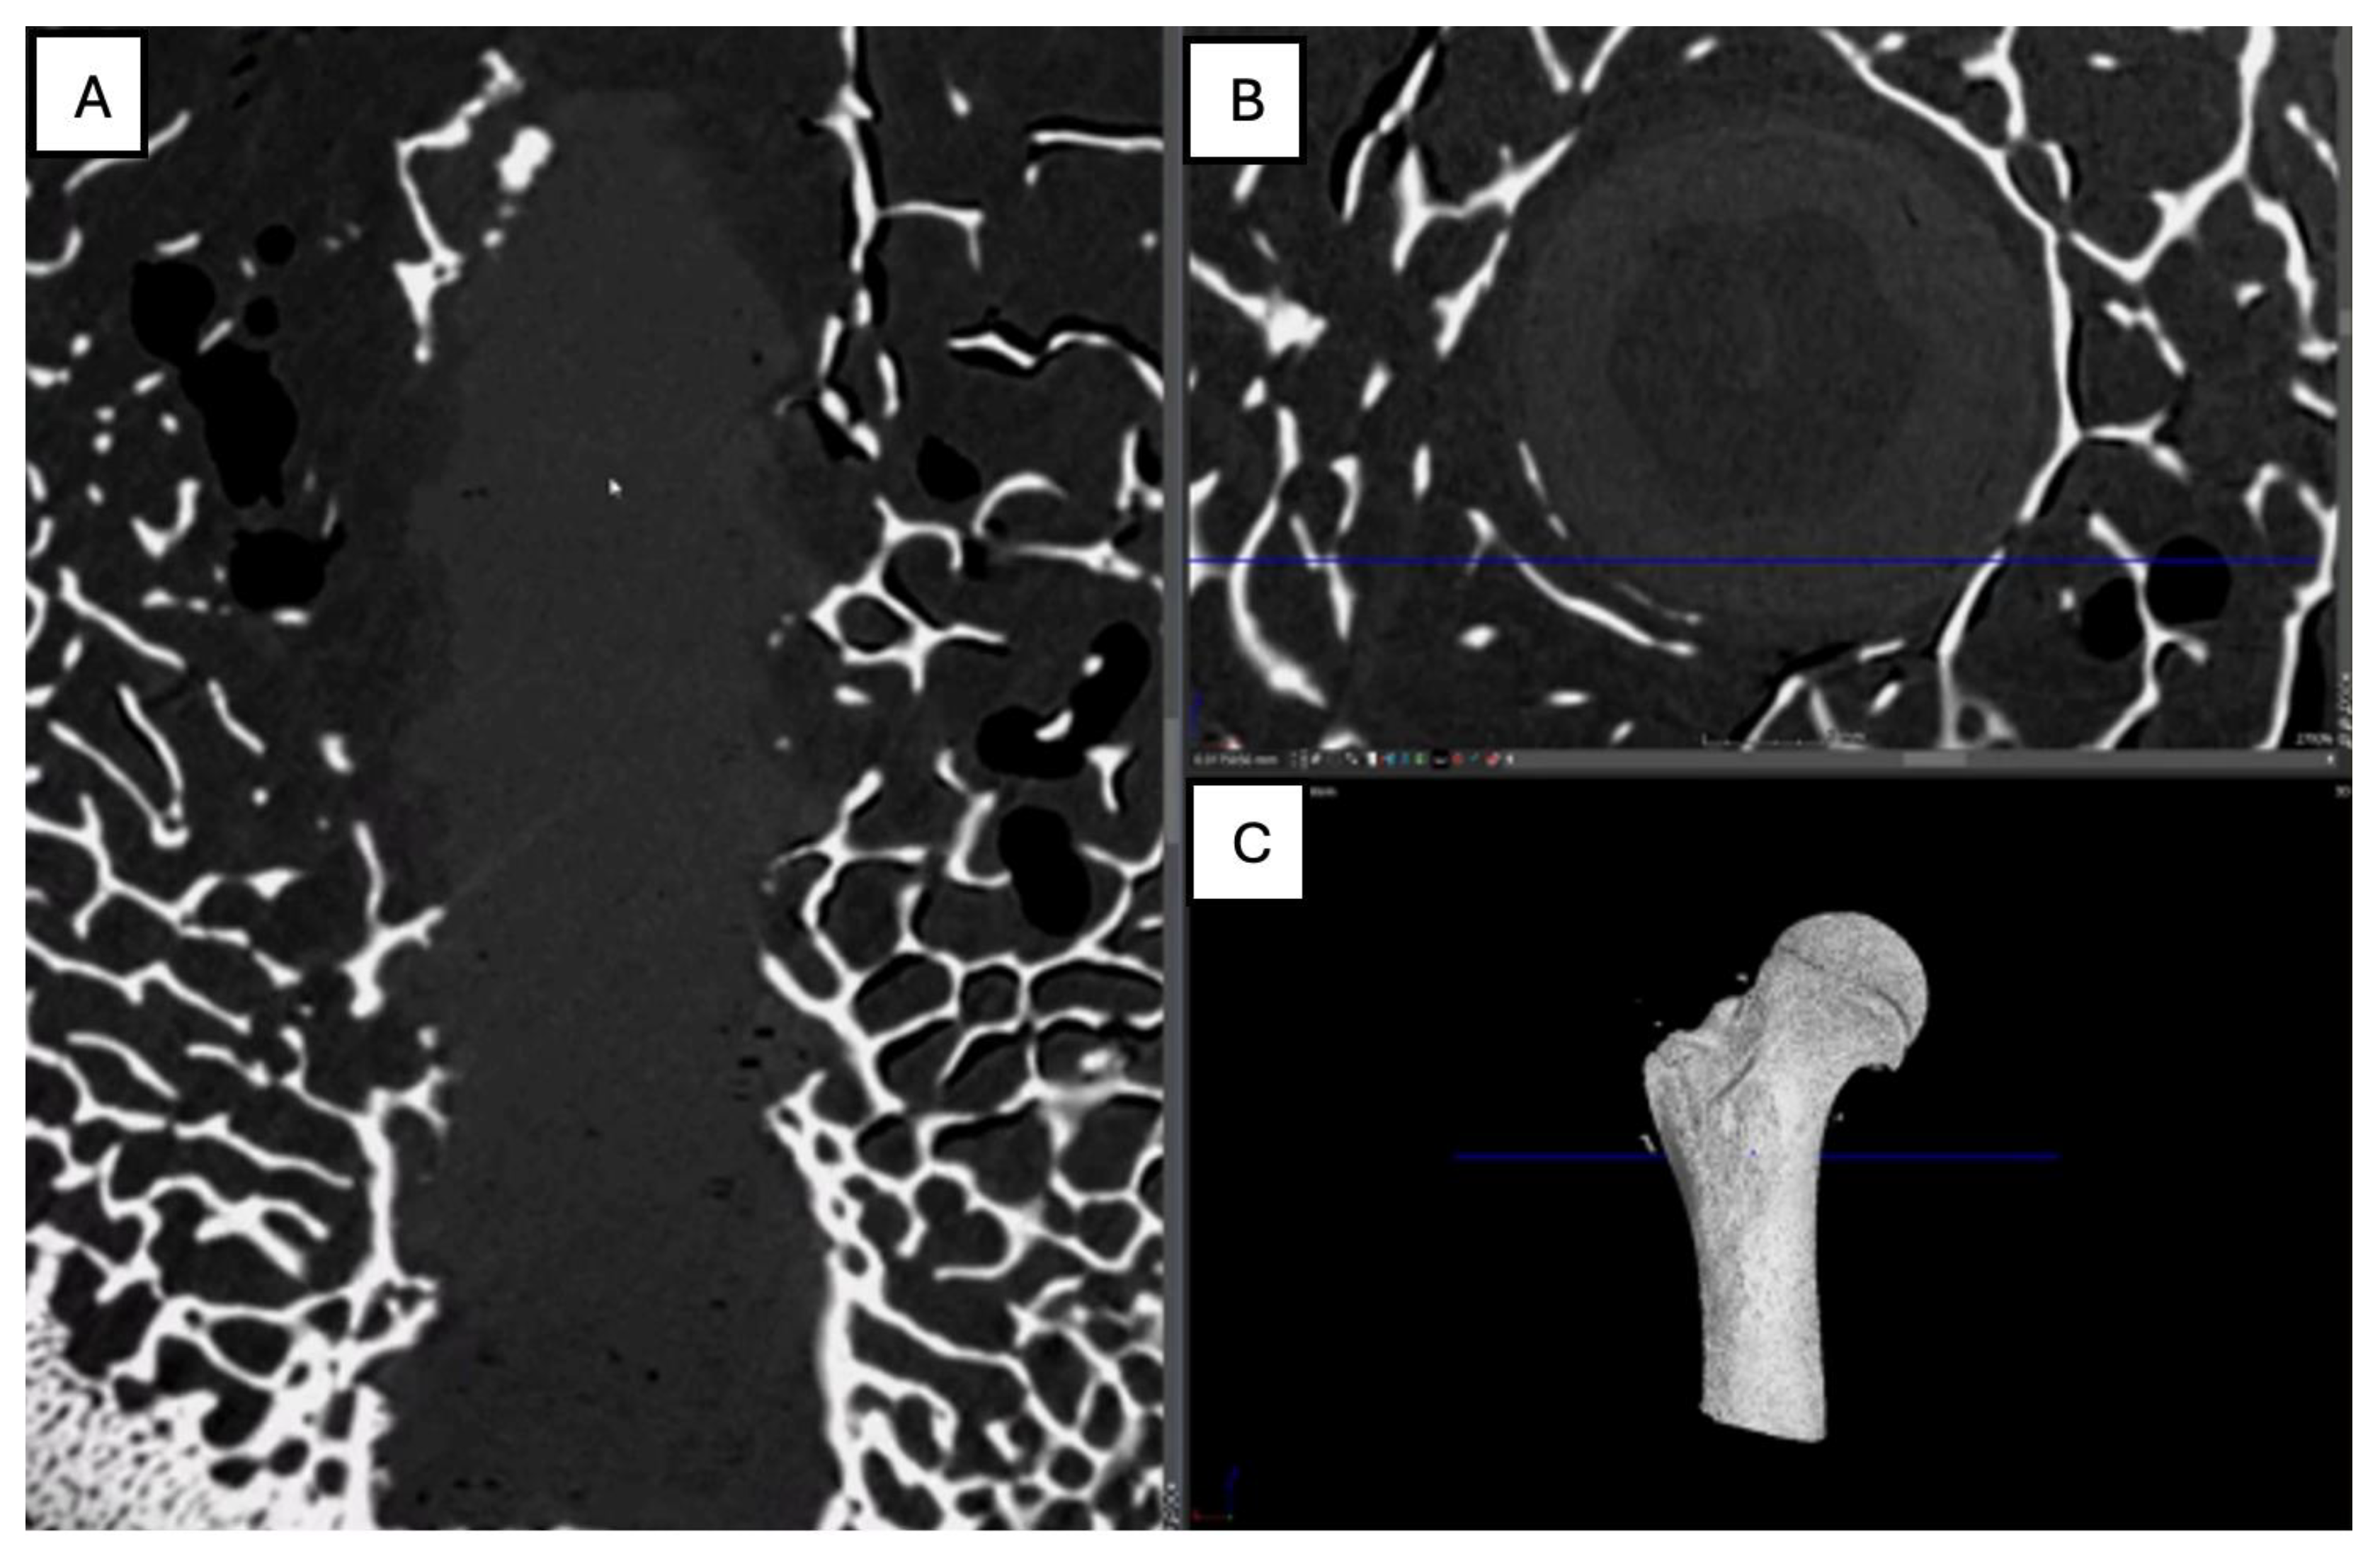

Figure 15. Computed tomography study (A) sagittal reconstruction (B) axial slice, and (C) 3D imaging of the left femur sample, two-month post-surgery, with PLA material.

PLA: A postoperative evaluation of the left femur of a porcine model was conducted at two months following implantation (Figure 15), utilizing axial cuts. Sagittal reconstruction, and 3D imaging. In the sagittal view revealed a slight increase in bone density accompanied by enhanced trabecular architecture. In the transverse slice, the PLA screw appears with a circular shape, with areas of higher density indicating mild bone growth around it. (Figure 15)

Figure 16. Computed tomography study of the right femur sample, two-month post-surgery, with PEEK material. (A) axial slice, (B,D,E,F) sagittal reconstruction, and (C) 3D imaging.

PEEK: In the 3D reconstructed presentation, the axial view shows the screw with a circular morphology, highlighting a hyperdense area in the middle third of the implant, indicative of bone growth within the screw. In the lateral view, a hyperdensity surrounding the screw is observed, reflecting bone growth that follows the shape of the insertion tunnel, accompanied by an increase in the surrounding trabecular bone. This pattern suggests an appropriate osteogenic response, with an ongoing implant integration process.(Figure 16)